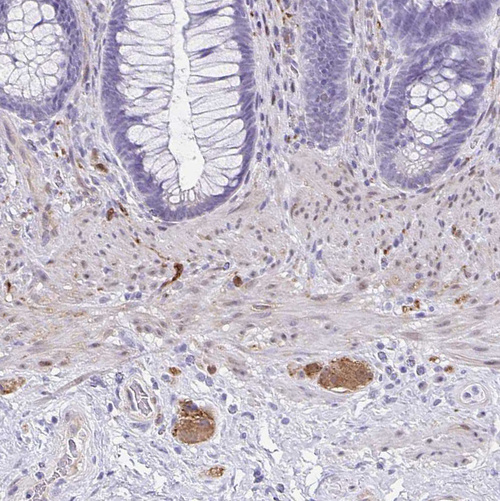

Immunohistochemistry analysis in human cerebral cortex and liver tissues using HPA036575 antibody. Corresponding TPPP RNA-seq data are presented for the same tissues.